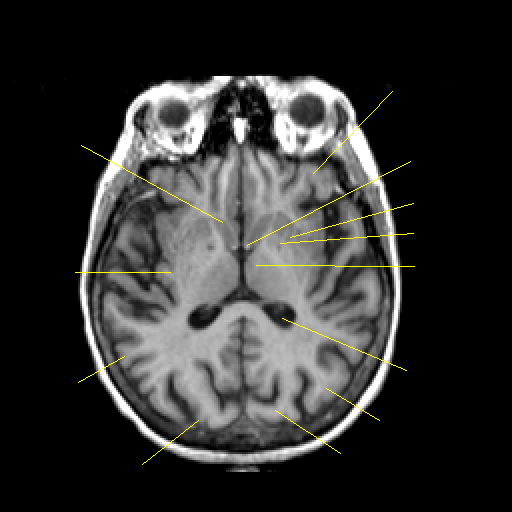

T1-weighted structural MR: Slice 28

Slice 28